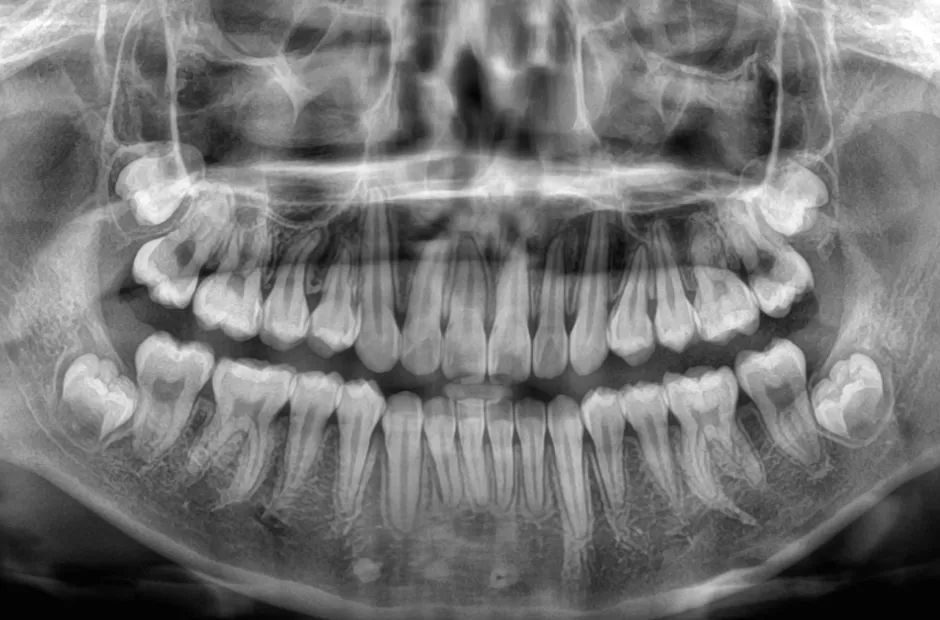

口腔内写真やレントゲンの撮影、歯型取りなど、口や顎の状態を詳しく把握するための精密検査を行ないます。さらに、骨の成長状況や身長・体重の増加傾向、永久歯の生えかわりについても確認します。

治療症例

ブラケット矯正

前歯部反対咬合

| 診断名・主訴 | 前歯部反対咬合 |

|---|---|

| 年齢・性別 | 14歳・男性 |

| 治療期間・回数 | 1年2か月 |

| 治療に用いた主な装置 | ブラケット矯正 |

| 抜歯部位 | なし |

| 治療費 | 60万円(税抜) |

| リスク・副作用 | 装置による違和感・疼痛・歯肉退縮・歯根吸収・虫歯のリスクなど |

治療前